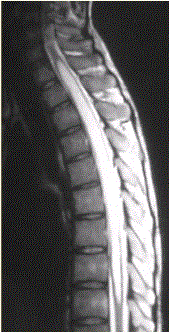

问题 患者女,45岁,胸部不适。影像学检查结果如下图所示。 关于成血管细胞瘤,正确的是

选项 A.脊髓内肿瘤 B.X线检查无阳性发现 C.明显增强的血管性壁结节对定性诊断价值 D.可多发,并伴发von-Hippel-lindau综合征 E.肿瘤上下或肿瘤内区域内见葡状生长的流空信号,可以确诊 F.发病率较低